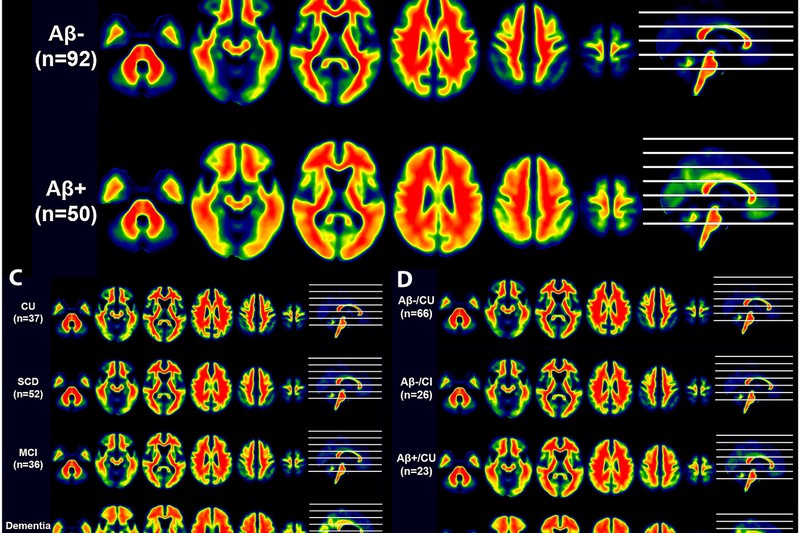

[18F]-D3FSP amyloid-β PET imaging in elderly adults and Alzheimer’s disease

Anqi Li, Ruiyue Zhao, Mingkai Zhang, Pan Sun, Yue Cai, Lin Liu, Guoyu Lan, Yalin Zhu, Xuhui Chen, Lizhi Guo, Yajing Zhou, Kun Sun, Lin Zhu, Hank F. Kung, Qingyong Wang, Linsen Xu, Ying Han, Xinlu Wang, Tengfei Guo

Dec 25, 2023 Alzheimer’s & Dementia DOI ↗